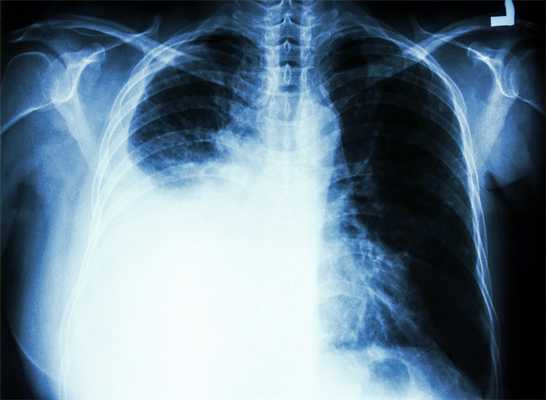

Плевральный выпот

Локализуется в полости плевры — защитной оболочки лёгких. Симптом сопровождается затруднением дыхания, болью в грудной клетке, чувством скованности груди. Образуется по причине болезней дыхания, пищеварения, сердца и сосудов, из-за травмирования плевры при ударах, неудачных операциях и уколах, а также при передозировке некоторыми препаратами.